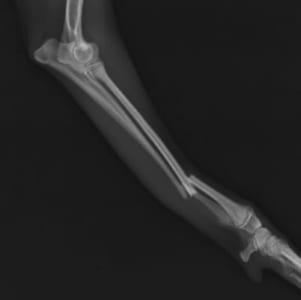

イタリアン・グレーハウンドの両前肢骨折

右前肢